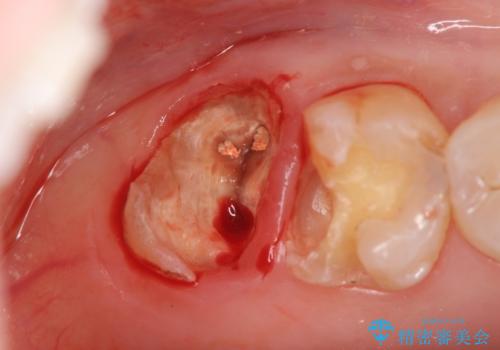

- ボクシング用のマウスガード(マウスピース)の作製を希望され来院されました。

ラグビーやボクシングなどのコンタクトスポーツは強い衝撃で歯を痛めてしまうことも多く、場合によっては歯を失ってしまうような結果になることもあります。

歯科医院で作る精度の高いマウスガードを使用することで大切な歯を守ることができます。